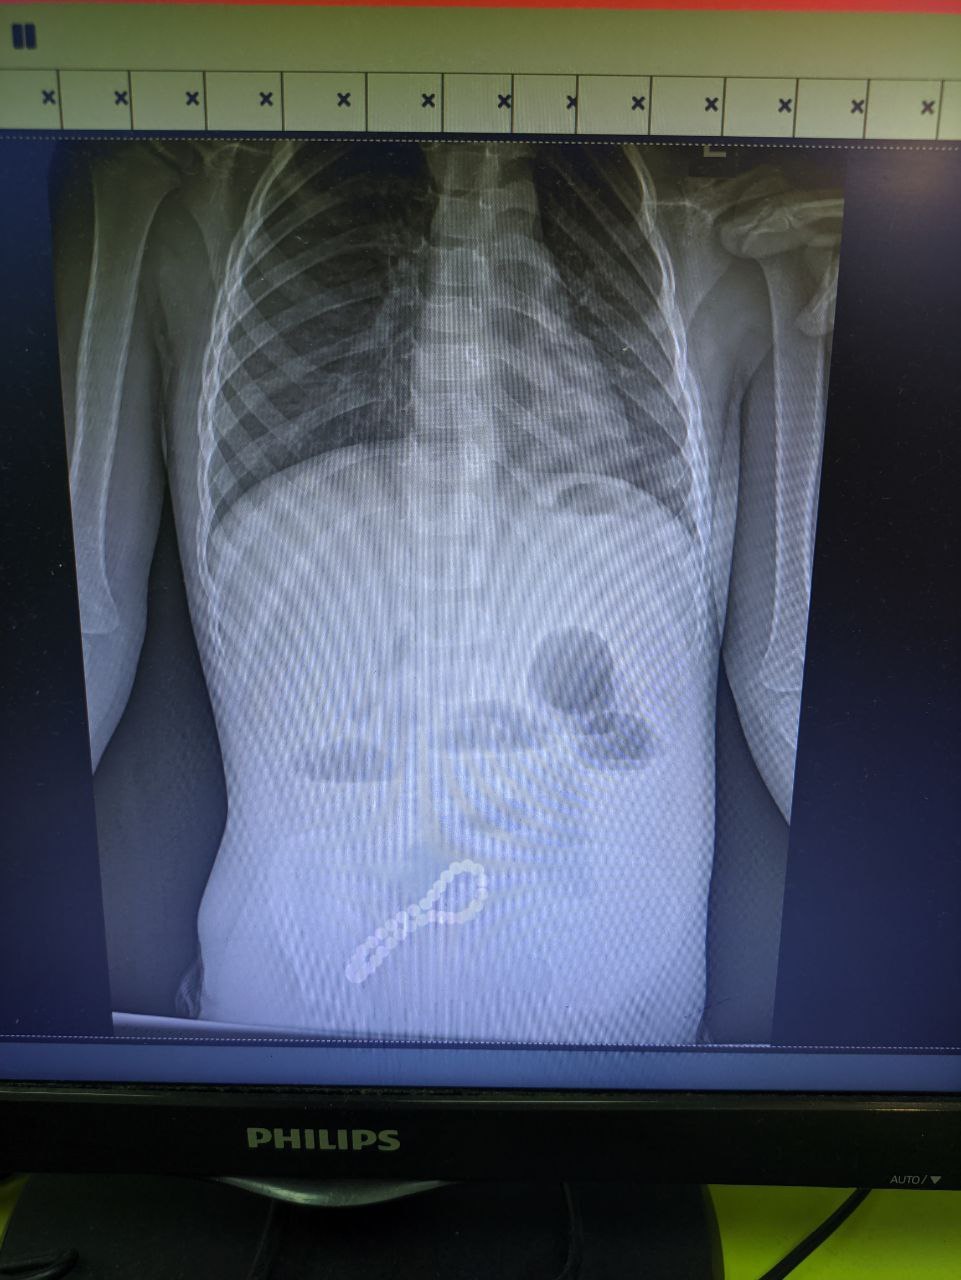

Пропажу браслета родители заметили не сразу, а вот нарушения работы желудочно-кишечного тракта у ребенка дали о себе знать очень быстро. Малыша госпитализировали в больницу. С помощью рентгена обнаружили в кишечнике инородное тело.

Хирурги провели минилапаротомию (через разрез передней брюшной стенки получили доступ к внутренним органам живота). Во время операции увидели, что магниты притянулись друг к другу и соединили петли кишки, в ее стенке – отверстия.